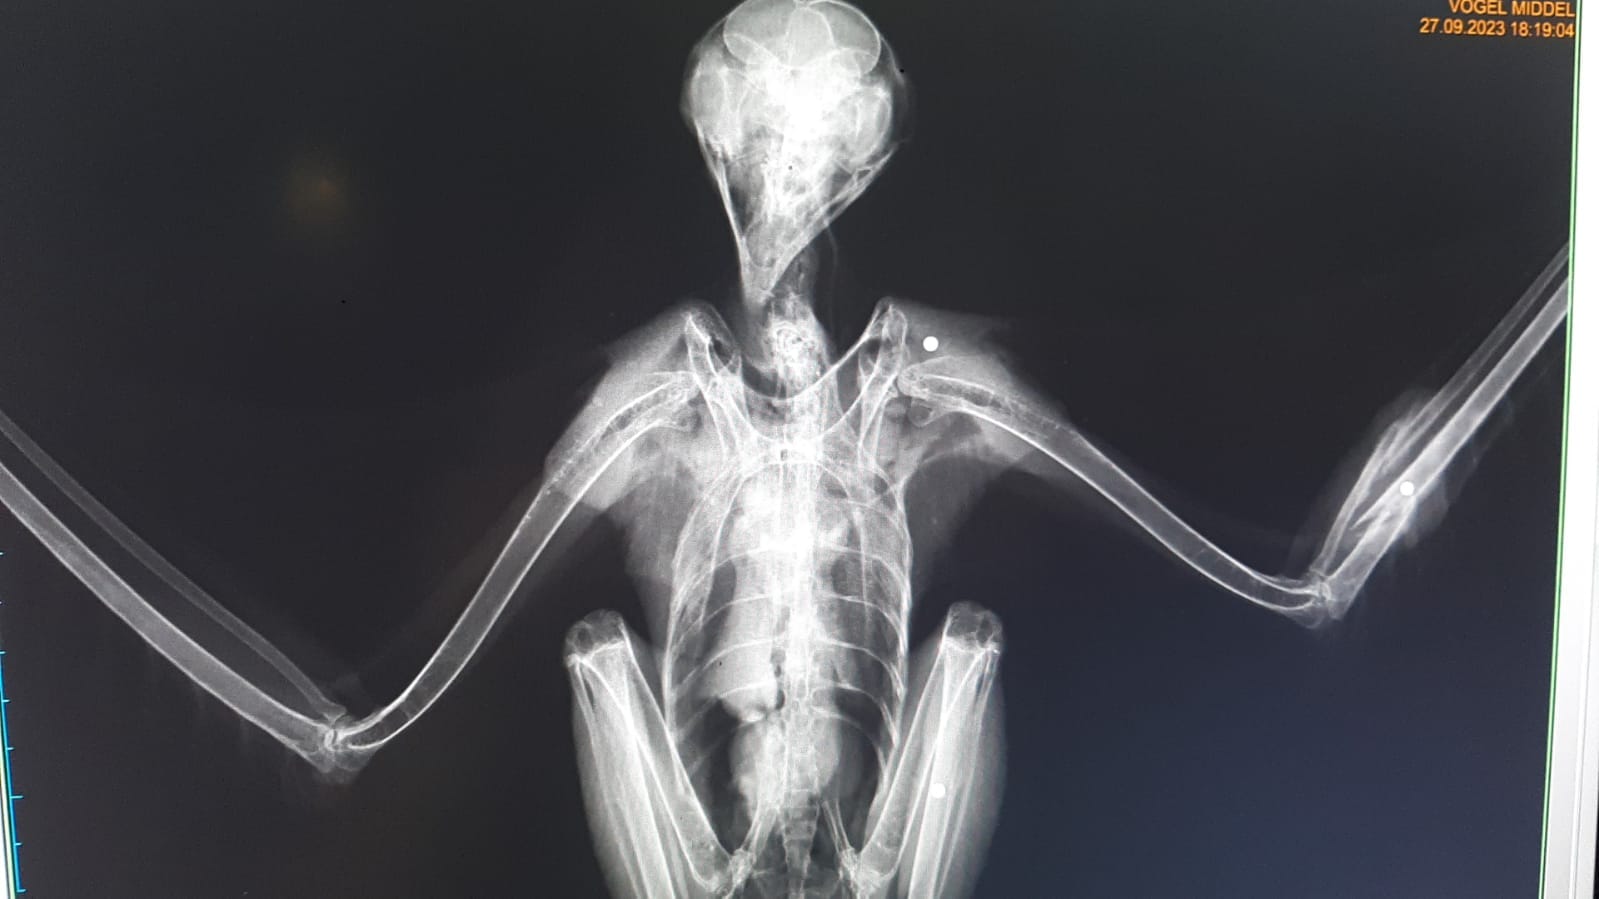

Na controle onder het röntgentoestel zagen we enkele hagelbolletjes zitten, geschoten dus. Onze dierenartsen bestudeerden de röntgenfoto's van de gebroken vleugel en besloten uiteindelijk om voorlopig geen operatie uit te voeren. De breuk zal extern gefixeerd worden en volgende week wordt er opnieuw gecontroleerd of de breuk zich goed herstelt. Indien niet kan een operatie alsnog nodig zijn.

En wat met de hagelbolletjes die nog in het lichaam zitten? Deze zullen daar blijven zitten en ingekapseld worden door het lichaam. Het verwijderen van de bolletjes zou te risicovol zijn en aangezien er geen vitale organen geraakt zijn, mogen ze blijven zitten.